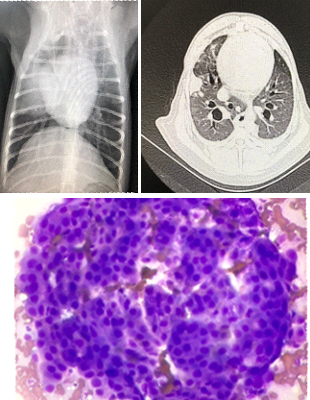

身体検査、尿検査、便検査、血液検査、血液化学検査、内分泌検査、超音波検査、 X線検査、CT検査、MRI検査、内視鏡検査、細胞診検査などにより現状を把握し、診断します。

がんの治療方法

*近年これに加え、免疫療法も選択肢の一つとなってきています。